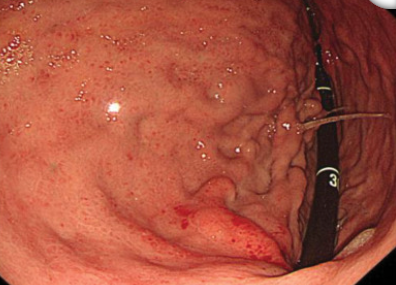

没多久,老周其余的检查结果也出来了。食管胃十二指肠镜检查(EGD)检查显示:

图1 患者EGD检查结果

胃底可见巨大、迂曲的静脉瘤(IGV型),且未见近期出血征象,这不是典型的肝硬化出血。那难道是脾脏的问题?白医生想到,而接下来的CT检查结果揭开了真相。